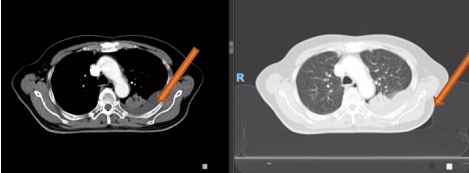

PET-CT(2020-08-13):食管胸下段管壁不均匀增厚,见放射性摄取增高,大小约18×14×27mm,SUVmax 14.6,符合食道癌表现。右侧肺门及纵隔(4R、5、7区)可见多个稍肿大淋巴结,最大约8×5mm,考虑炎性淋巴结可能性大。

左肺上叶尖后段团块状密度增高影,PET见放射性摄取增高,大小约40×29×31mm,SUVmax 28.0。病灶跨越左侧斜裂胸膜生长,密度均匀。左肺上叶胸膜下可见多发微小结节状密度增高影。建议治疗后复查,必要时活检排外恶性肿瘤的可能。

胸部平扫+增强CT(2020-08-27):食道中段管壁增厚,上下累及约4.5厘米(约胸5/6椎间隙水平至胸8椎体上缘水平),增强后可见轻度强化,隆突下见境界不清淋巴结。左肺上叶尖后段及相邻左肺下叶背段交界处见团块状直径约2.5厘米软组织密度灶,边缘可见毛刺,左侧胸腔积液,左下肺膨胀不全。右肺下叶见少许条状影。结论:1、食管癌。2、左肺上叶尖后段病灶,符合肺癌。左侧胸腔积液,左下肺膨胀不全。